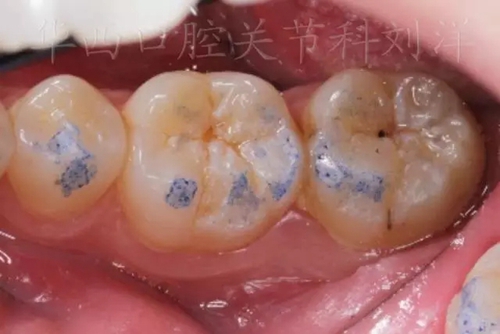

▲圖6:200µm 功能運(yùn)動(dòng)

② 然后換用40微米紅色咬合紙,牙尖交錯(cuò)位咬合

▲圖8:40µm 正中咬合

③ 結(jié)果:

9.webp.jpg

▲圖9:最終結(jié)果